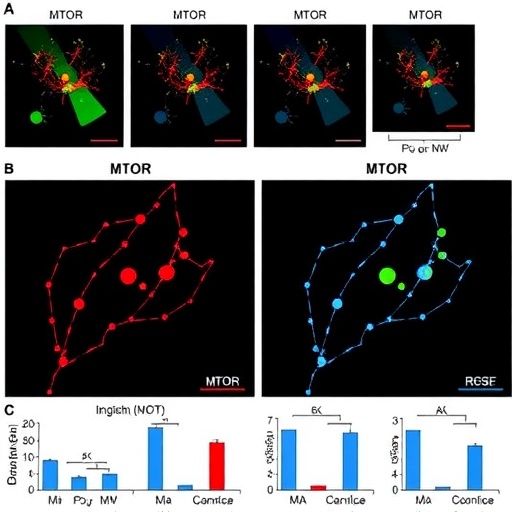

The team employed advanced genomic analyses, including single-cell RNA sequencing and epigenomic profiling, to map the landscape of regulatory variation within immune cells isolated from patients suffering pneumonia-induced sepsis. These cutting-edge methodologies enabled the identification of rare regulatory polymorphisms influencing MTOR transcription and downstream signaling cascades. The analysis revealed that certain regulatory variants diminish MTOR expression in neutrophils, which in turn limits their ability to orchestrate effective communication with T cells. Neutrophils, renowned for their rapid response to infection, thus become less capable of activating T cell responses critical for adaptive immunity, highlighting a fundamental roadblock in the host defense against pneumonia pathogens.

Functional assays further validated that neutrophils carrying these MTOR regulatory variants exhibited depressed cytokine secretion profiles and impaired expression of co-stimulatory molecules key for T cell activation. This immunological dampening effect translated into a measurable deficit in T cell proliferation and cytokine production—hallmarks of a robust adaptive immune response. These findings illuminate how genetic heterogeneity in immune regulation can directly influence clinical outcomes, providing a possible genetic explanation for the variability in sepsis severity and mortality observed across patient populations.

Mechanistically, the authors propose that reduced MTOR signaling in neutrophils cripples their metabolic reprogramming and effector functions, which are essential triggers for recruiting and activating T cells. The diminished neutrophil-T cell crosstalk undermines the generation of effective immunological memory and pathogen clearance, setting the stage for persistent infection and systemic inflammation. In this light, MTOR emerges not only as a metabolic regulator but as a pivotal node modulating intercellular communication during immune activation and resolution phases of sepsis.

Moreover, the findings underscore the interplay between innate and adaptive immunity at a molecular level. Neutrophils, traditionally seen as short-lived and more innate in function, are shown to influence the adaptive arm by modulating T cell activation through mTOR-dependent pathways. This concept challenges existing paradigms and calls for revisiting immune cell classification and communication in the context of infection and inflammation.